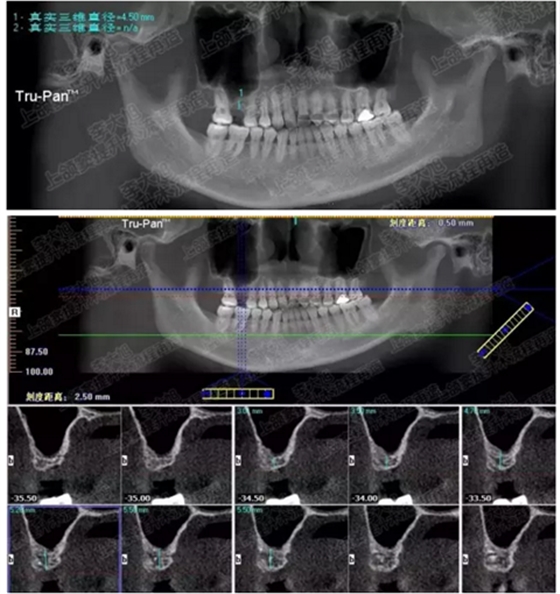

病例三

剩余骨量3mm

005.png

006.png